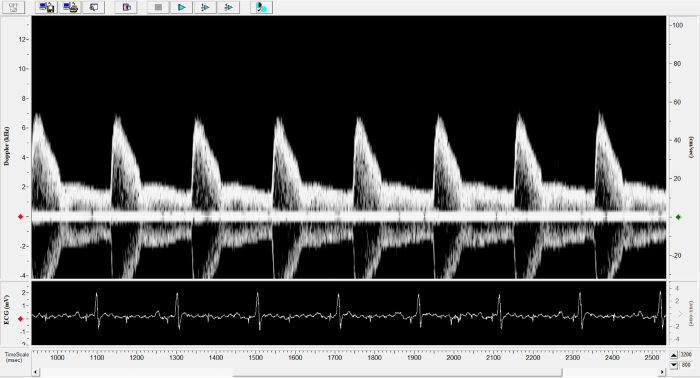

Imaging gallery - Doppler Flow Velocity System

Mouse - TAC Procedure Imaging. Image Credit: Scintica Instrumentation Inc.